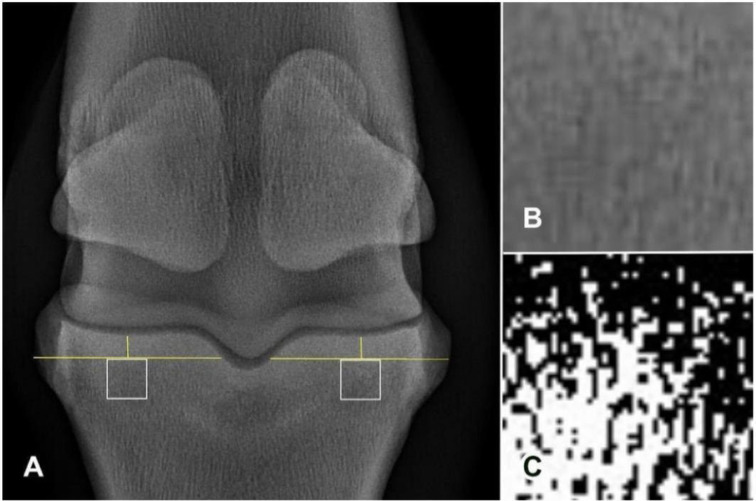

骨关节炎(OA)是马的一种常见病,会导致骨小梁结构和放射纹理发生变化。虽然分形维度(FD)和裂隙度已被用于量化人类的这些变化,但它们在马匹中的应用仍处于起步阶段。本研究评估了分形维度、骨面积分数(BA/TA)和裂隙度在量化近节指骨(P1)骨小梁差异中的应用,共对 50 例不同 OA 程度的马掌指关节进行了射线检查。在背侧视图中,在近端骨骺的骨小梁、P1矢状沟的内侧和外侧定义了感兴趣区域。在严重OA马的内侧观察到较低的BA/TA值(P=0.003)。不同OA程度的马在FD和裂隙度方面没有明显差异(P>0.1)。FD、BA/TA和裂隙度不能有效识别不同掌指关节OA程度马匹P1骨小梁的放射纹理变化。

Osteoarthritis (OA) is a prevalent condition in horses, leading to changes in trabecular bone structure and radiographic texture. Although fractal dimension (FD) and lacunarity have been applied to quantify these changes in humans, their application in horses remains nascent. This study evaluated the use of FD, bone area fraction (BA/TA), and lacunarity in quantifying trabecular bone differences in the proximal phalanx (P1) in 50 radiographic examinations of equine metacarpophalangeal joints with varying OA degrees. In the dorsopalmar view, regions of interest were defined in the trabecular bone of the proximal epiphysis, medial and lateral to the sagittal groove of P1. Lower BA/TA values were observed medially in horses with severe OA (P=0.003). No significant differences in FD and lacunarity were found across OA degrees (P>0.1). FD, BA/TA, and lacunarity were not effective in identifying radiographic texture changes in the P1 trabecular bone in horses with different metacarpophalangeal OA degrees.